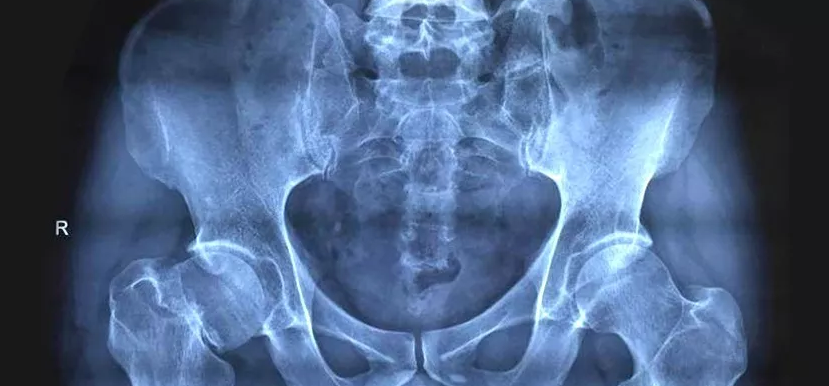

众所周知 , 股骨头病变坏死 , 治疗困难 , 一旦患上这种病 , 就基本与致残、致瘫不远了 。

1.股骨头坏死的早期症状

股骨头坏死的早期有五大主要症状这五大主要症状分别是下肢无力、下肢畏寒、腰部疼痛、臀部疼痛、膝关节部疼痛 。

股骨头坏死早期的五大症状都不在髋关节上这些症状出现的频率还不相同 , 几天有症状几天没有症状 。